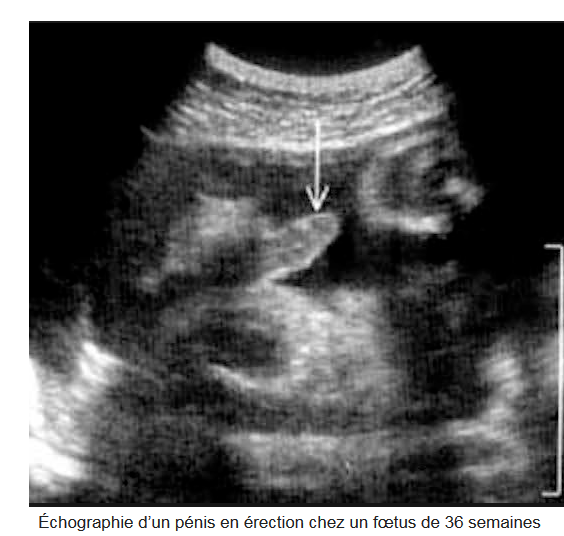

Dès sa naissance, le nouveau-né expérimente sa sexualité! Celle-ci est présente dès la vie intra-utérine et se développe tout au long de la vie, bien qu’elle s’exprime différemment selon l’âge.

Le terme « l’érection » signifie le processus au cours de laquelle l’organe sexuel masculin se remplit involontairement de sang. On peut observer l’érection le matin, le soir ou à tout moment de la journée. Toutefois, certains représentants du sexe masculin se demandent pourquoi l’érection arrive le plus souvent le matin.La réponse est simple – le matin la concentration des hormones atteint son plus haut degré dans le corps masculin.L’érection matinale représente une réponse physiologique du corps (l’organe sexuel masculin est observé se trouve en état excité) et constitue une preuve d’une santé forte de l’homme. Elle ne signifie pas sa promiscuité sexuelle ou son obsession du sexe.L’"auscultation" de ses érections matinales et nocturnes renseigne chacun d’entre nous, messieurs, sur l’état de notre santé vasculaire, cœur compris.Tant que persistent les "matins triomphants" chers à Victor Hugo, il est probable que notre système cardio-vasculaire soit sain.Les érections matinales sont le prolongement direct des érections nocturnes. Purement réflexes, elles vont être plus facilement perçues si le dormeur se réveille durant une phase de sommeil paradoxal. Elles seront à l’inverse moins ressenties par les hommes ayant des rythmes de sommeil décalé.